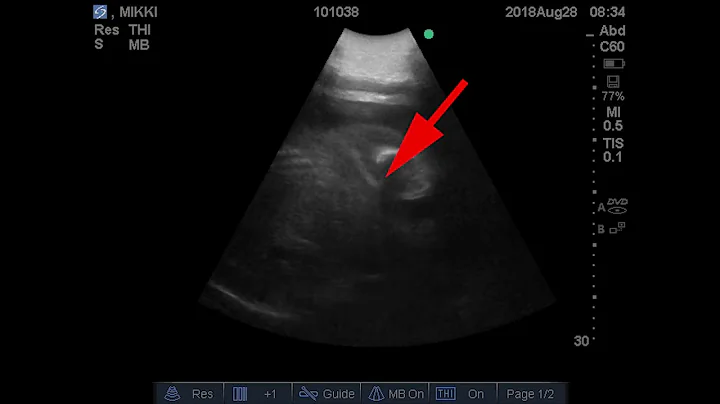

Mikki The Elephant Gets An Ultrasound At Louisville Zoo

Mikki has another 11 months left of her pregnancy, which was planned through artificial insemination.